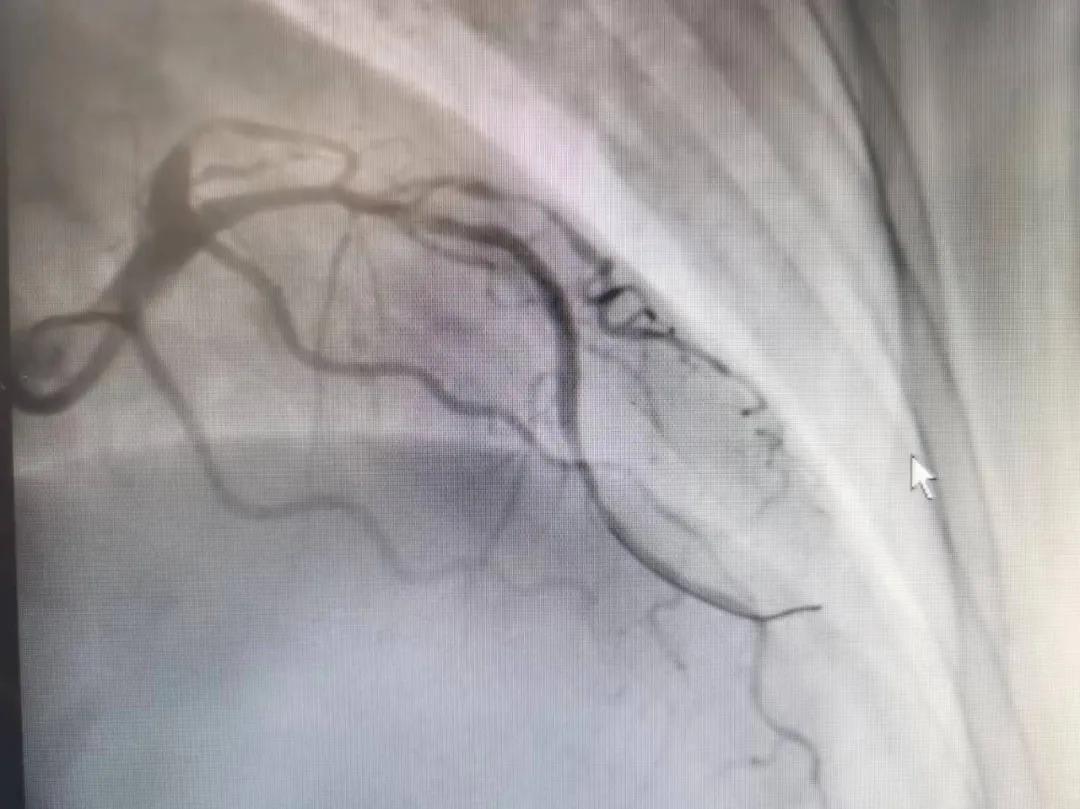

王瑾院長和李慧新主任帶領(lǐng)介入團隊充分評估,決定行前降支冠狀動脈鈣化病變旋磨術(shù),術(shù)中應(yīng)用1.5mm旋磨頭,以15萬-17萬轉(zhuǎn)/分速度共對病變旋磨3次,累計旋磨時間60秒,后復(fù)查造影示鈣化明顯減輕,為后續(xù)操作創(chuàng)造了良好條件,隨后應(yīng)用預(yù)擴張球囊、切割球囊再次處理病變,并順利植入支架1枚,復(fù)查造影顯示支架膨脹及貼壁良好,無夾層、血腫、慢血流等情況,手術(shù)順利完成。患者術(shù)后無不適,胸悶、胸痛癥狀明顯緩解,順利出院。

術(shù)后